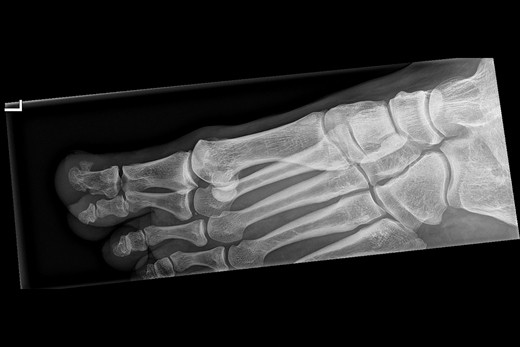

Patiënt A, een 12-jarige jongen, heeft sinds een jaar een zwelling onder de nagel van de rechter grote teen. Aanvankelijk denkt de huisarts aan verruca vulgaris, maar de huidafwijking verdwijnt niet na behandeling met vloeibare stikstof. Histologisch onderzoek wijst op een bloedblaar. De huisarts verwijst de patiënt naar de dermatoloog. Subunguaal aan de rechter grote teen is sprake van een onscherp begrensde, bruine -hyperkeratotische nodulus van 0,6 cm, die de nagelplaat omhoogdrukt. De laesie voelt hard aan. De klinische diagnose luidt digitale exostose [figuur 1]. De dermatoloog laat een röntgenfoto maken, waarop een subunguale exostose aan de tuft van de grote teen van de rechtervoet te zien is [figuur 2]. De patiënt krijgt een verwijzing naar de orthopedisch chirurg voor excisie. Histologisch zijn er geen aanwijzingen voor een maligniteit.

Figuur 2 | Een X-voet (laterale opname) van patiënt A.

Een X-voet (laterale opname) van patiënt A.